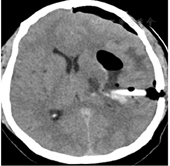

开颅手术组:患者全麻下在颞部行弧形切口,避开大血管及神经,遇到出血时及时仔细止血。根据患者血肿量及脑组织水肿程度判断骨瓣的大小,星形切开硬脑膜,并沿脑回方向切开脑皮质直至血肿区。在显微镜下清除血肿,遇到粘连较紧的血块时无须清除,观察有无残腔渗血,放置引流管,并根据脑组织肿胀程度考虑是否行回复骨瓣,严密缝合肌肉皮下及皮肤。两组术后24 h内复查头颅CT(图5),并给予相同治疗方案。